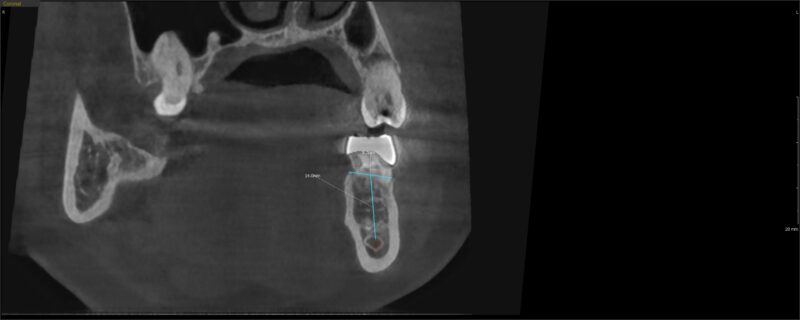

I saw the pt today and felt like the bone could be more dense in the extraction site. Looking at the photos you can see that the ridge was 9.7mm and now it’s 7.8mm after 4 months.

As far as size selection, I would be comfortable with a 4-4.5 mm width and a 8mm length. The position of your ruler over the site is not exactly on the bone (the lines extend out a little bit) so I would rather be a bit more conservative.